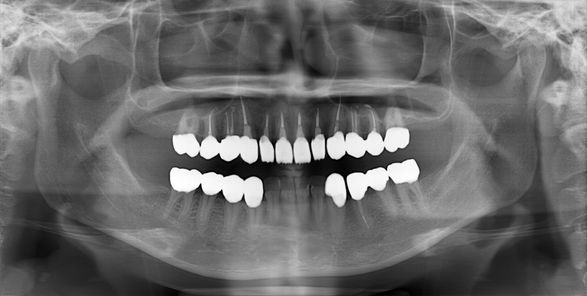

様々な歯科医院で治療を断られて名取歯科医院にご来院された患者さんの治療が終了しました。今回の治療で一番の喜びは当たり前かもしれませんが、キレイに治療ができたことです。

そしてもう一つ非常に重要なことがあります。それは歯科インプラント治療を施さなくて良かったことです。この患者さんはインプラントをすることで、新たなリスクが懸念されたためです。具体的な理由はここでは割愛させていただきますが、患者さんへのインプラント治療を避けられたことは、歯科医師として大変嬉しいことでした。